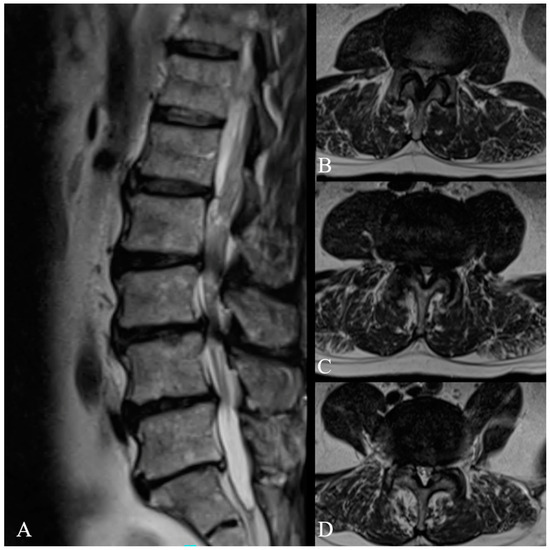

- Giorgi, P.D.; Pallotta, M.L.; Legrenzi, S.; Nardi, M.; Andrea, M.; Schirò, G.R. Spinal cord compression in thoracolumbar burst fractures: Application of high-definition three-dimensional exoscope in minimally invasive lateral surgery. Eur. J. Orthop. Surg. Traumatol 2023, 33, 2173–2177. [Google Scholar] [CrossRef]